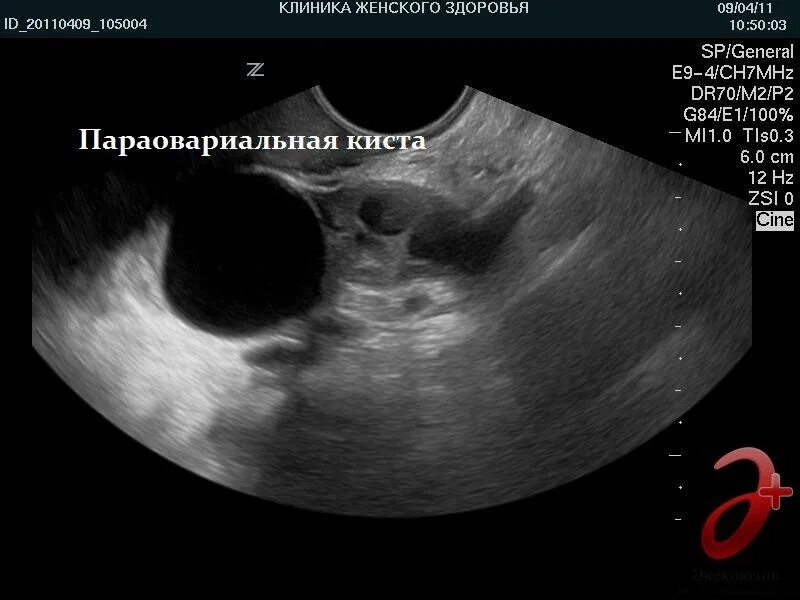

Как выглядит яичник